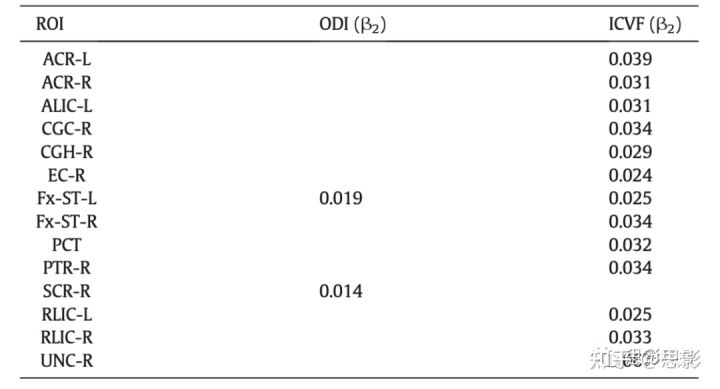

回归模型2的β2显著(Eq.8),则表明存在显著的性别差异。一些ROIs上有显著的性别差异,并且大多数显著性出现在NODDI模型的扩散指标中:ODI和ICVF(表2)。年龄相关的关键ROI中ICVF和ODI的回归线绘制在图3中,以显示在年龄纵向变化中的性别差异。男性大脑的ODI在左侧穹窿终末纹状体和右侧放射上冠处明显增大约7%(ODI绝对值约为0.017)。在13个ROI中,男性的ICVF显着高于7%,包括易受年龄影响的解剖结构(即扣带回的右前段、扣带回的右海马段、双侧穹窿-终纹和右侧钩状束)。7%的ICVF对应于0.04的绝对差异。DTI和P0在回归模型的斜率中没有显示出显著的性别差异。

表2 在模型2(Eq.8)中,扩散指标和ROI与显著的β2配对,表明性别差异是纵向偏移的,而不考虑老龄化因素。